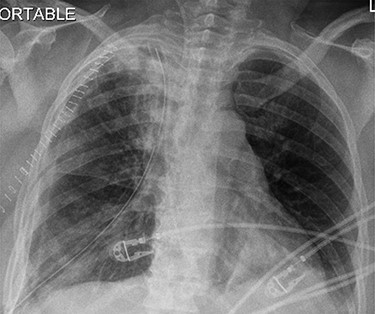

Surgery consisted of a right thoracotomy through the fifth intercostal space. The mass was found to be compressing the three lung lobes of the right lung, and no gross mediastinal invasion appreciated. Mass excised using a combination of blunt dissection and cauthery. An anterior and posterior thoracostomy tubes were left in place. Final dimensions of the mass were 19.2 cm × 17.5 cm × 10.5 cm (See Fig. 5). After mass excision right lung collapse was evident (See Fig. 6). Then after right lung ventilation, all three right lobes expanded (See Fig. 7). Postoperative CXR was also consistent with full right lung re-expansion (see Fig. 8).

Postoperative CXR revealing complete lung expansion, no associated pneumothorax, no effusion.